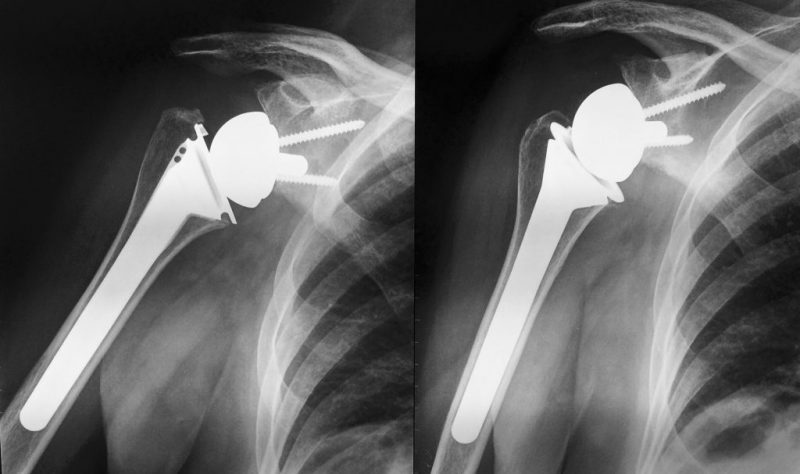

È in aumento in Italia il numero delle persone che hanno necessità di impiantare una protesi di spalla per eliminare il dolore e migliorare i movimenti per cercare di rispondere alle esigenze di questi pazienti e per un proficuo aggiornamento su metodiche e materiali, il dottor Ariberto Di Felice, responsabile dell’ortopedia della Casa di cura Pierangeli di Pescara, ha stato organizzato il convegno “Il ruolo della protesi di spalla, problematiche e soluzioni oggi”. La due giorni, che si è svolta a Città Sant’Angelo, ha messo a confronto specialisti del comparto privato, pubblico e universitario di diverse realtà italiane.